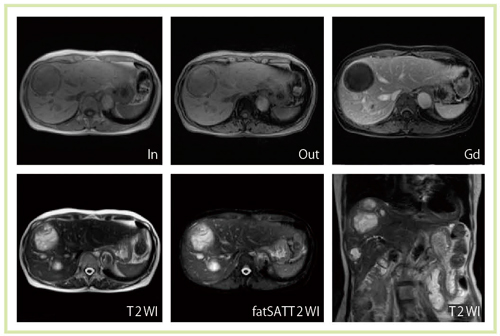

また,3T MRIでは,RF磁場の不均一が増大するという大きな問題がある。このため,3T MRIが登場して以来,頭部領域などでは有用性が高いものの,腹部領域や循環器領域への適用は難しいとされてきた。メーカー側もこの問題の解決に取り組んでおり, Multi-phase Transmissionと呼ばれる技術が開発された。RF強度分布を均一化して,画像ムラを低減する技術である。東芝メディカルシステムズでは,本邦初の3T装置に,現在世界でも最もスペックの高い,RFアンプ2台,4ポート給電を採用した(図2)。Titan 3Tでは,この技術によって画像ムラを低減した画像が得られるようになり,従来,3T MRIの課題であった上腹部,胸部領域の撮像にも適用できるようになった(図3,4)。

図4 乳がんの多発肝転移症例(Titan 3T)

3T MRIによる心臓は,susceptibility artifactの影響やSAR(specific absorption rate)の制約のために,従来は撮像が困難な領域であった。しかし,Titan 3Tでは非常に明瞭な画像が得られている(図5〜8)。

図14 肝細胞がん症例(Titan 3T) 肝細胞相 TR/TE=3.7/1.3 MX=588*640 NS=100 ST=2 Time=19s

図14 肝細胞がん症例(Titan 3T)

肝細胞相

TR/TE=3.7/1.3 MX=588*640 NS=100 ST=2 Time=19s